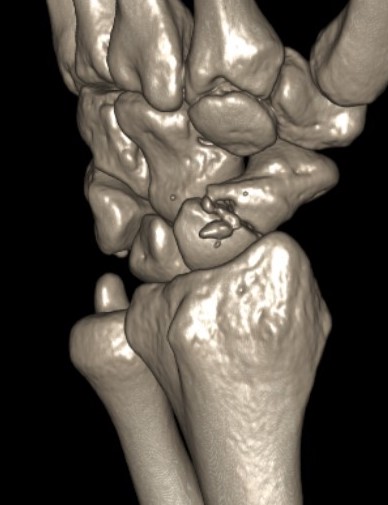

CT

Trans-scaphoid perilunate dislocation

Perilunate dislocation